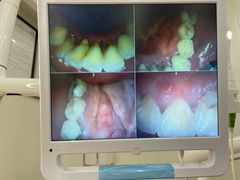

• 牙博士口腔品牌连锁(杨浦店)

• -牙博士口腔品牌连锁(杨浦店)

Ulquiorra | 21-01-12

报错